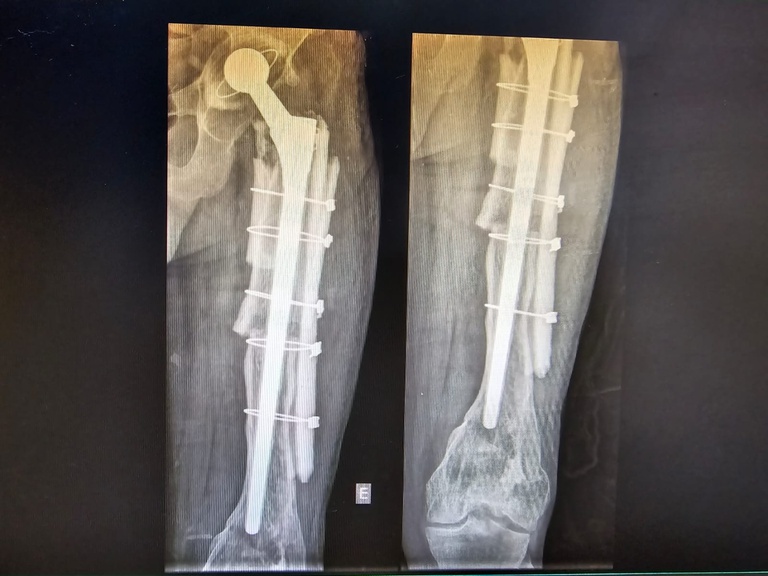

“O procedimento foi um sucesso. Conseguimos reconstruir o fêmur e corrigir o encurtamento do paciente com o uso de uma haste femoral de revisão e réguas ósseas. O paciente andou no mesmo dia da cirurgia, não precisou de UTI e não precisou de transfusão de sangue. Está no sexto mês de pós-operatório, sem dor e sem queixas. Vida normal”, comenta o médico ortopedista do HU-UFMA, Raul Almeida, que é o responsável técnico pelas equipes de transplante de tecido ósteo-condro-fáscio-ligamentoso do HU.

Juarez Sousa foi o 20º de 21 pacientes já beneficiados por esse tipo de transplante no HU-UFMA, desde 2016, quando recebeu a habilitação, sendo o único no Estado a realizar esse procedimento. “O paciente encontrava-se com muita dor e limitação funcional por soltura de prótese e perda óssea extensa no fêmur. Em março, realizamos a cirurgia de revisão de artroplastia total do quadril esquerdo com reconstrução do fêmur com uso de 2 réguas ósseas”, explica Raul Almeida.